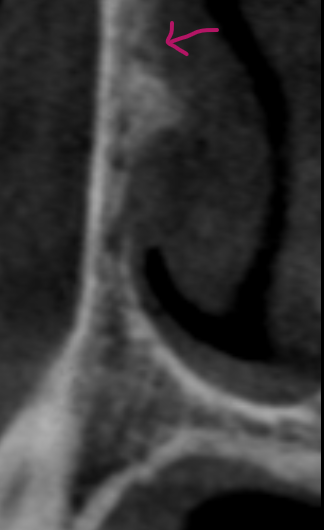

TMJ joint spaces and condylar bone: Due to the small size and complex morphology of the temporomandibular joint.

However, the main challenge is that the bony parts of the joint — like the condylar head and the thin bone of the glenoid fossa — often have fine features smaller than a typical CBCT voxel.

- Small holes or bone erosions may be hidden or smoothed out, making early disease hard to spot.

- Joint surfaces can look thicker, rounder, or flatter than they really are.

- Measurements of bone thickness or joint space may be inaccurate.

- Minor TMJ changes from arthritis, trauma, or developmental issues could be missed or misrepresented.

This is especially important for TMJ problems because many joint conditions begin with tiny changes in bone that are difficult to see unless the scan has very small voxels.